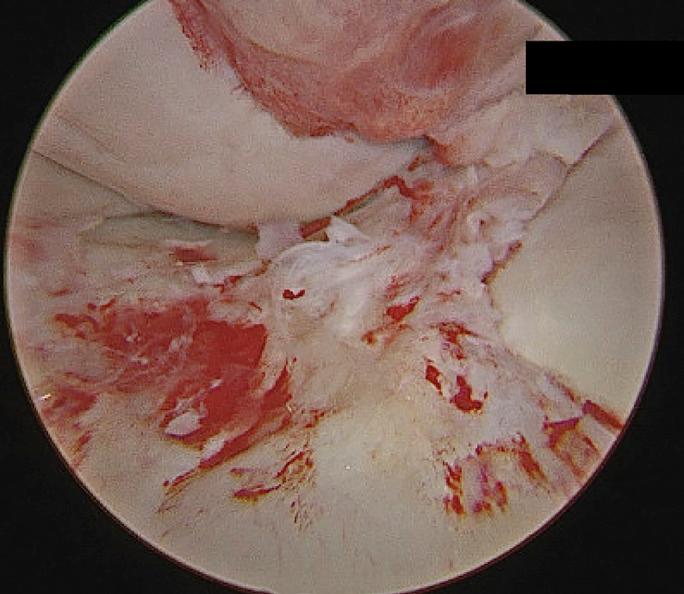

A 16-year-old woman presented with acute on chronic knee pain and instability following a twisting injury. The tibial insertion of the anterior cruciate ligament (ACL) was nonvisualized on magnetic resonance imaging. A cord-like ACL, originating from the lateral intercondylar notch and inserting smoothly into the anterior horn of the intact lateral meniscus, was found on arthroscopy. Her ACL was reconstructed with quadriceps tendon autograft.

一名16岁女性在扭伤后出现慢性膝关节疼痛急性发作及膝关节不稳。磁共振成像显示前交叉韧带(ACL)的胫骨附着点不可见。关节镜检查发现一条索状ACL,起自外侧髁间切迹,平滑地插入完整外侧半月板的前角。她接受了自体股四头肌肌腱ACL重建术。